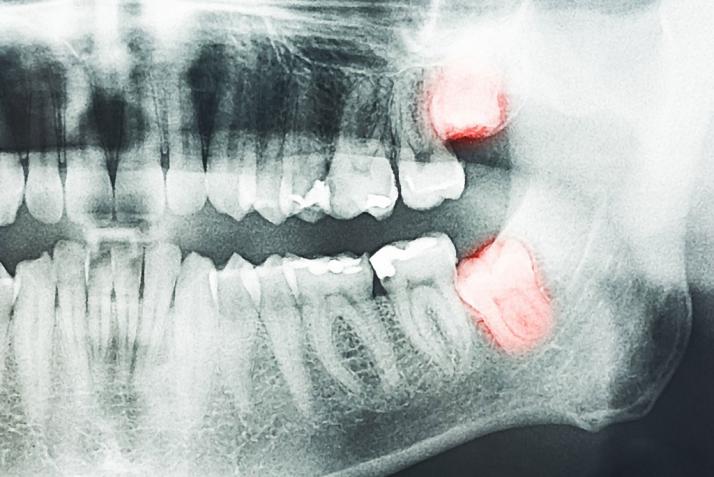

Extraction of a wisdom tooth requires minor oral surgery. Most dentists could perform this surgery. If the case is too complicated it may require the expertise of an oral surgeon. Before a surgery, you would be explained of the procedure, duration and post operational risks like swelling, pain and trismus clearly. Dentist would also take a radiograph (X ray) of the tooth before the surgery to ensure your safety.

When this tooth is erupting you will experience pain, discomfort and swelling. These problems could be controlled by medicines. Usually wisdom teeth are fully formed when they erupt and the jaw is also fully grown at the same time, thus, there would not be enough space for them to erupt fully. They could be slanted, angulated, partially or fully embedded in bone and exposing only a small portion in the oral cavity. These made them difficult to notice. Because of these incorrect positions, usually they are non functional. Because of certain angulations, there may be food impaction causing tooth decay, foul breaths and gum diseases. These problems could also spread to the adjacent second molar if left untreated.

Most of the time when the second molar is affected, decay usually happens at the neck and root portion. The only way to save this tooth is through root canal treatment. This is a complex treatment and it does not guarantee a full recovery of the tooth. Therefore, extraction of a problematic wisdom tooth is a wise decision.